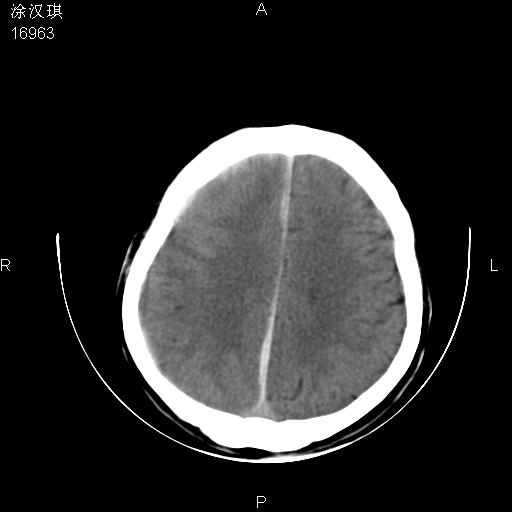

以下是引用chinazhouhua在2008-5-1 12:06:00的发言:[br]影像上来看,这是个典型的硬膜下血肿,包括右侧额颞部、大脑镰下、小脑幕下,而且在右侧额颞顶枕部、大脑镰下没看到高密度出血向脑沟内延伸,但是小脑幕下硬膜下有时候和蛛血不是很好鉴别,而且硬膜下很多时候伴有蛛血,往往在复查的时候出来,所以这种病人还是应该考虑硬膜下血肿伴有蛛血。

以下是引用zsl6918在2008-5-1 15:34:00的发言:[br]本病例主要表现为急性硬膜下血肿。